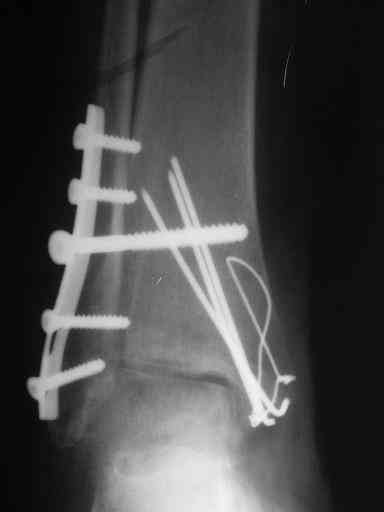

Завершая презентацию случая хотим показать результат операции. Прооперировали больную в соседнем отделении. На операции выраженый рубцовый процес в области синдесмоза, остеопоротические изменения в области медиальной и латеральной лодыжек. Провели удаление рубцовой ткани, остеосинтез медиальной и латеральной лодыжек с позиционным винтом на синдесмоз. Фото прилагаем. Благодарим за отзывы.